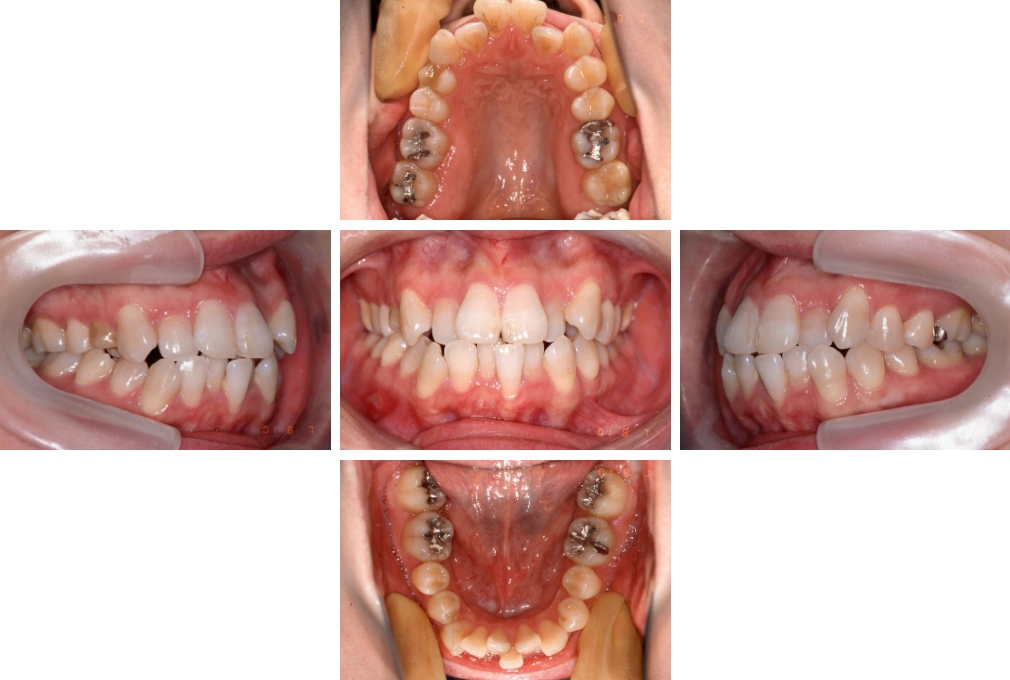

CASE:04

アングルⅢ級傾向を持つ叢生

初診時年齢 22歳

性別 女性

治療費の目安 105万円程度(治療開始時)

上顎右側犬歯が唇側に転位していることを主訴に県内歯科医院から紹介来院された。骨格的にはⅢ級傾向で上顎右側犬歯が唇側転位となり、側切歯が口蓋側に転位していた。下顎前歯が叢生になっていることも相まって上下の正中線は右側に大きくずれていた。アングルⅢ級傾向を持つ上下顎前歯部叢生と診断した。

上下顎小臼歯を抜歯していただき上顎舌側、下顎唇側マルチブラケット装置を使用して動的治療を行った。矯正用ゴムの使用など協力状態も良く、正中線の大きな移動があったのも関わらず2年10カ月で装置を撤去し保定へ移行した。保定移行後14年が経過し、ご息女の診察でご来院いただいていたことから、口腔内を拝見したが、下顎前歯のわずかなずれがあったものの大きな歯列の乱れはなく歯列は安定していた。動的治療期間2年10カ月間。

治療前

22歳6か月

治療後

動的治療期間2年10カ月間

25歳6か月

治療終了

動的治療終了後2年2カ月

28歳8か月

14年経過

動的治療終了後14年7カ月

40歳1か月